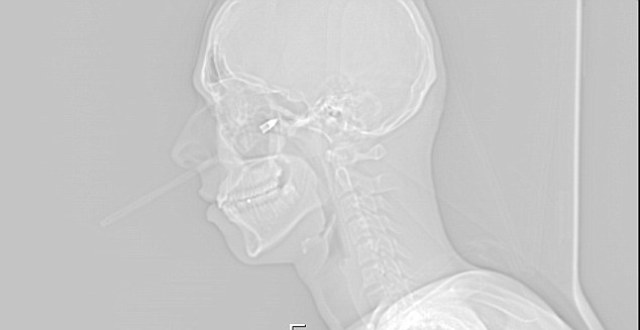

Παρά το σοκ που και οι δύο υπέστησαν, ο φίλος του τον μετέφερε άμεσα στο νοσοκομείο, όπου η ακτινογραφία έδειξε μόνο ένα σπασμένο κόκαλο και ως εκ θαύματος δεν είχε προκληθεί ζημιά σε κάποιο, ζωτικής σημασίας, νεύρο.

Συγκεκριμένα οι γιατροί ανέφεραν ότι λίγα εκατοστά πιο πάνω ή πιο κάτω και ή θα είχε πεθάνει ή δε θα μπορούσε να ξαναμιλήσει ποτέ.